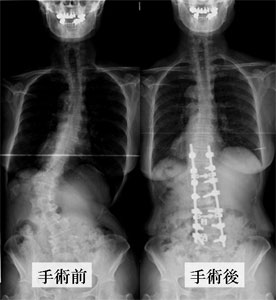

側弯症の治療法

治療法は1.定期的経過観察、2.装具療法、3.手術の三つに分けられます。

- 手術に関しては、別ページにてご紹介いたします。詳しくはこちら⇒手術のご紹介をご参照ください。